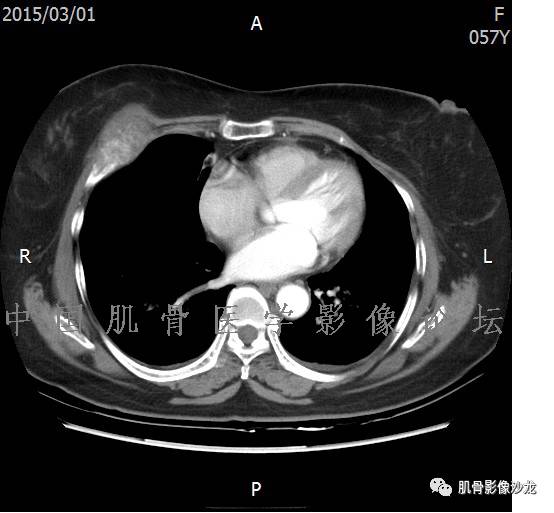

1、软骨肉瘤可以有膨胀性骨质破坏(病例3,4),可以有溶骨性骨质破坏(病例2),局部皮质因为破坏变薄,中断 ;

2、软骨基质T2WI高信号,软骨小叶分叶状,也就会出现高老师提到的骨内膜扇贝形压迹。一般认为骨内膜扇贝形压迹超过骨皮质厚度的2/3是软骨肉瘤在长管状骨的特征性表现。如上图。3、软组织肿块或肿胀;

4、 钙化,环形,弓形,边缘模糊 ;

5、增强后进行性延迟,不均匀分割状强化, 会强化的纤维间隔,软骨小叶不会强化,关于老师们说到的钙化,软骨肉瘤不一定会有钙化 。

悦水仙 :教科书上讲,软骨肉瘤10s内强化,而骨软骨瘤是延迟强化,二者不同, 增强后进行性延迟,不均匀分割状强化,怎么理解?

葛英霖:我理解就是分化越好的软骨,延迟时间越长才能看到强化,个人感觉

郝大鹏: 软骨小叶常规时间不强化,延迟几个小时会强化。常规时间内强化的是小叶间隔